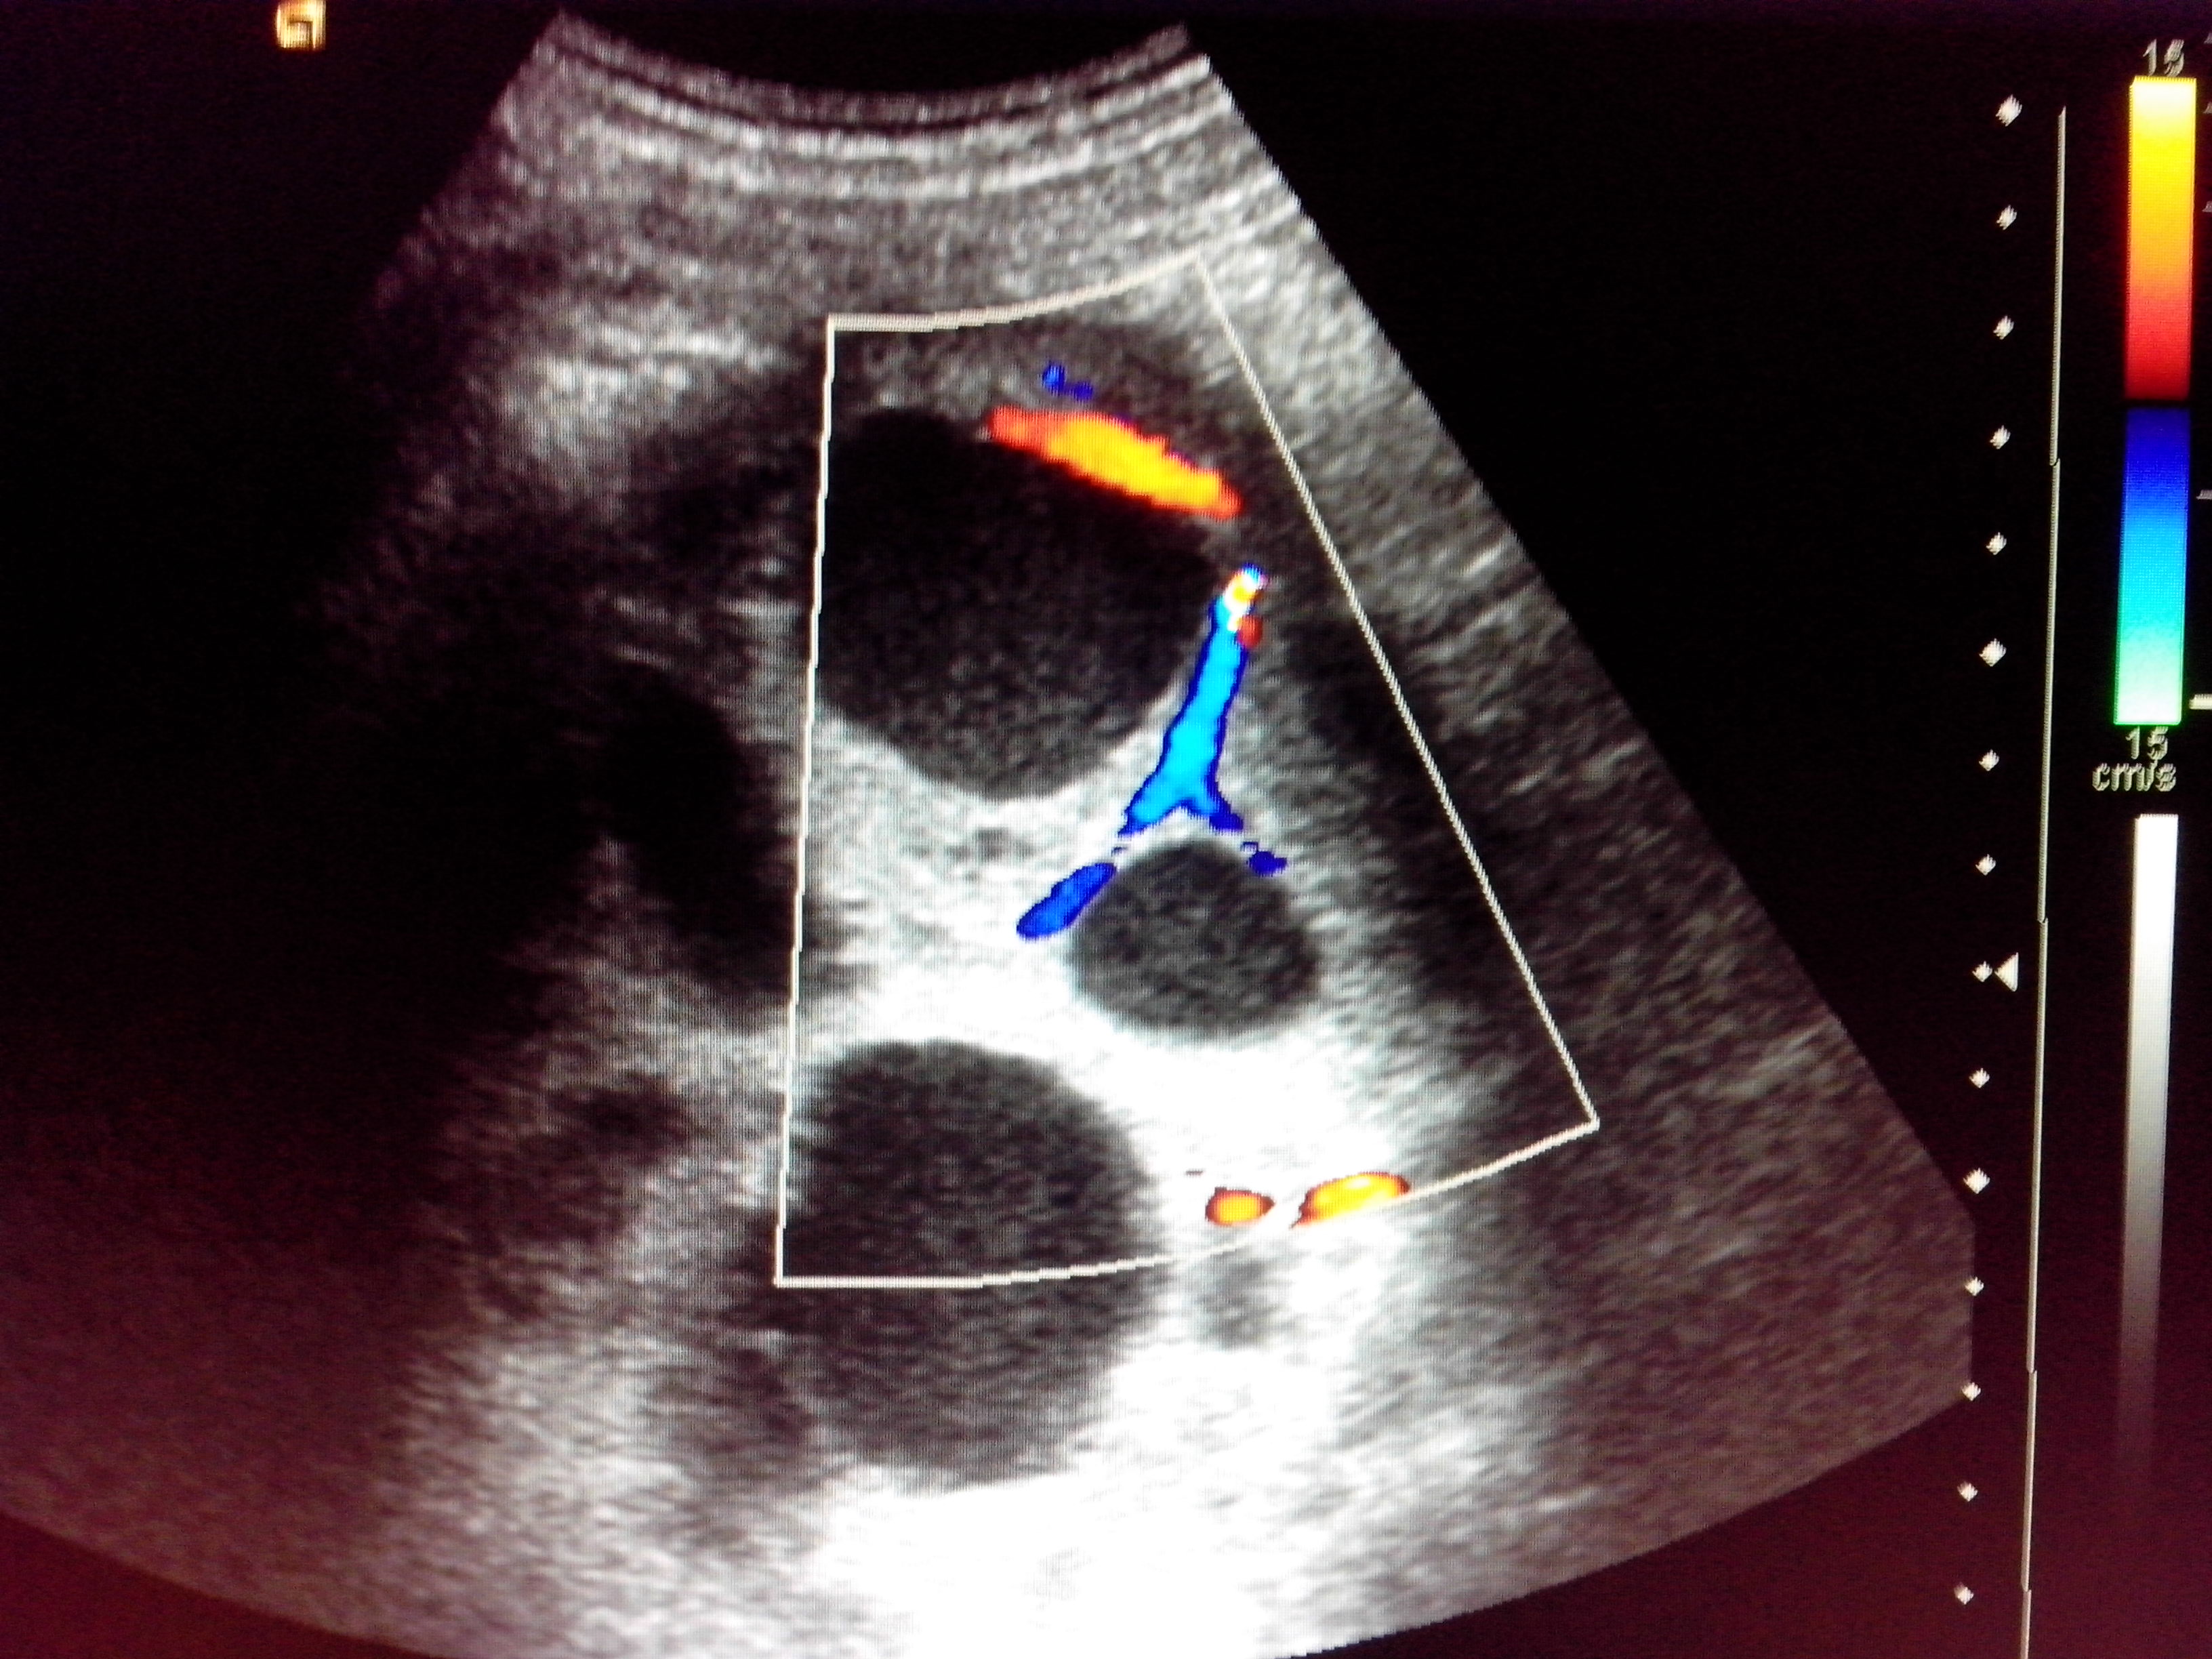

| В пользу опухоли свидетельствуют множественные сосуды в перегородках и капсуле | ![]() ![]() ![]() |